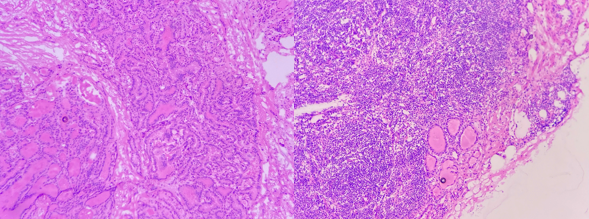

Hình 1. Chẩn đoán Ung thư biểu mô tuyến giáp thể nhú di căn hạch

bằng sinh thiết tức thì ngay trong cuộc phẫu thuật.